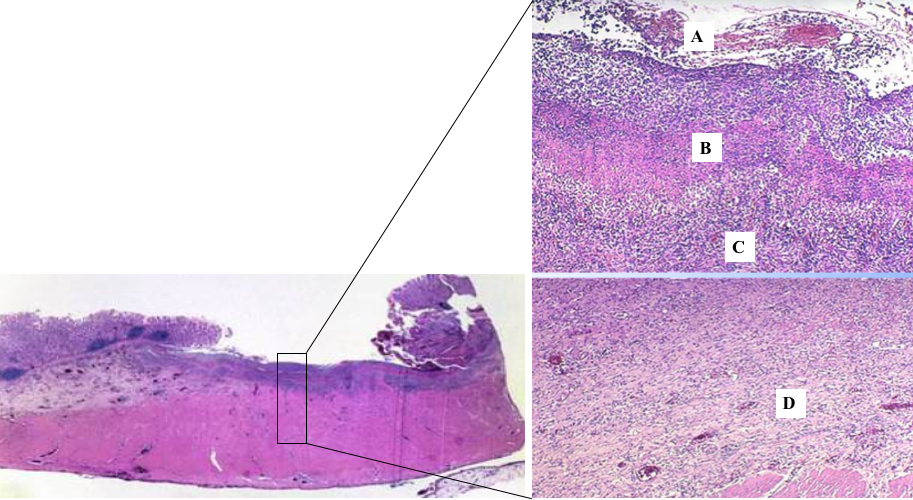

镜下,活动性溃疡的底部由表面至深层分四层:①渗出层(A):由不等量的急性炎性渗出物如嗜中性粒细胞和纤维素等构成;②坏死层(B):由坏死的细胞,组织碎片和纤维蛋白样物质构成的凝固性坏死;③肉芽组织层(C);④瘢痕层(D)。瘢痕层内可见中、小动脉管壁增厚、管腔狭窄及血栓形成 (增生性动脉炎)。另可见神经节细胞和神经纤维变性或增生,有时可形成创伤性神经瘤。溃疡壁处可见粘膜肌层和肌层的粘连或融合。